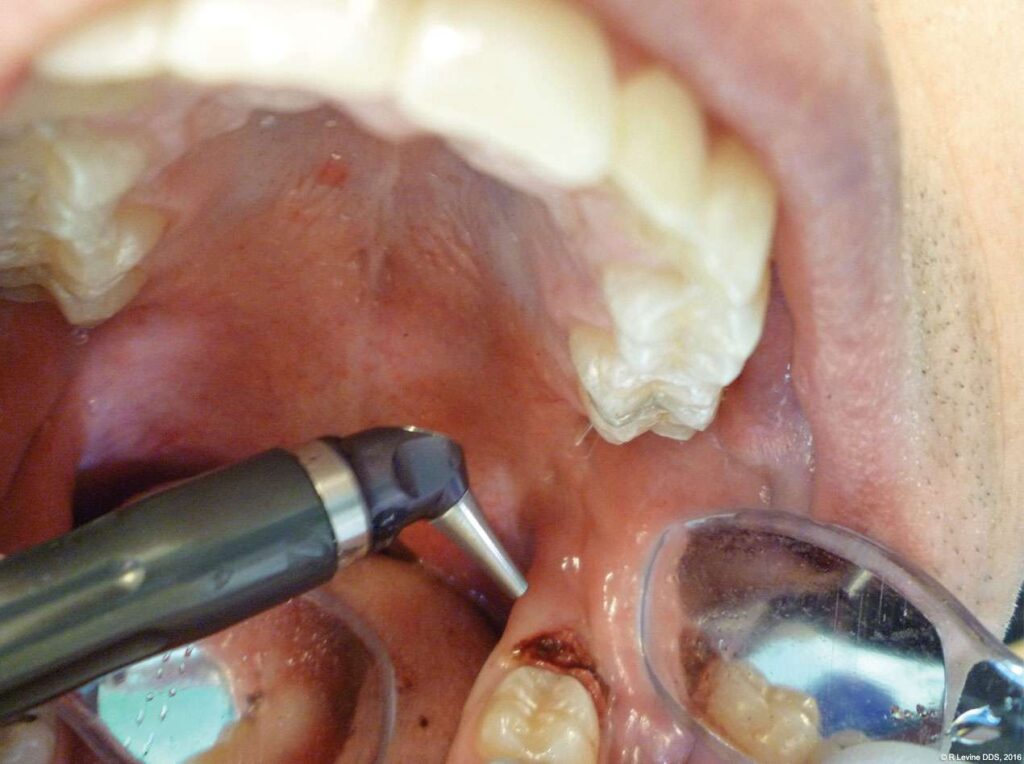

- After the initial pass with the laser, the inflamed gingiva bled slightly and the surgeon defocused the beam by increasing the nozzle-to-tissue distance to quickly obtain hemostasis (Figure 6). Note the excellent visualization and the clear operatory field.

- Additional tissue around the primary surgical site was superficially ablated to “feather out” the wound and make the treated area blend with the healthy gingiva better (Figure 7).